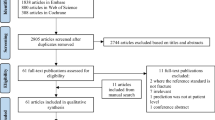

In this contribution we will review the published literature with respect to vertebral fracture assessment and determination of BMD from CT scans in the context of opportunistic screening. Chest, abdominal and pelvic CT scans are among the most frequent clinical CT scans that can be exploited. The value of OS in osteoporosis has been recognized already a couple of years ago as the identification of subjects with a high fracture risk promises a considerable reduction of the burden of osteoporotic fracture. Osteoporosis is mostly a disease of subjects above 50 years of age, for which also the frequency of CT scans increases rapidly.